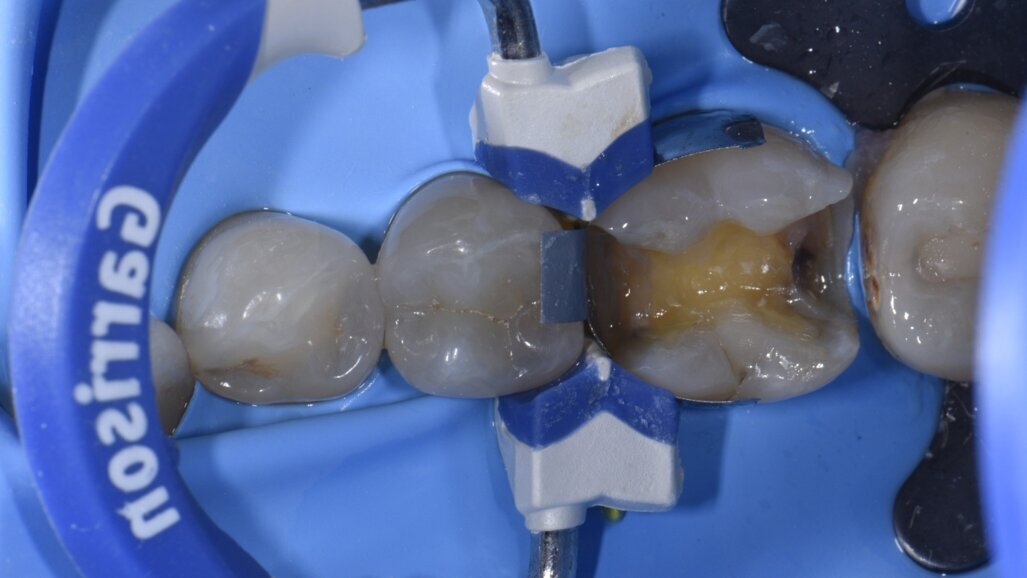

Per questo caso è stato scelto il Garrison Slick Bands (FX100) di dimensioni premolari, a causa della leggera microdonzia. Le dimensioni delle Slick Bands devono essere selezionate in modo tale che, a pieno posizionamento apicale, il limite occlusale della Band coincida o vada leggermente oltre il livello desiderato della cresta marginale. È stato posizionato un cuneo (FXYL) per fissare le Slick Bands e il sigillo marginale cervicale controllato in questa fase. Se dovessero verificarsi degli spazi vuoti con il posizionamento dell’anello di tensione (FX400), ciò richiederebbe la rimozione dell’anello e l’utilizzo del nastro in PTFE nell’area del vuoto prima di sostituire l’anello di tensione.

Come primo passo, si è scelto di ricostruire la parete mesiale (Fig. 3). Microstrati di un A2 fluido (Majesty esthetic, Kuraray Noritake) sono stati posizionati dopo un approccio di tipo total etch con MPa Bond (Clinicians Choice). A questo è stato permesso di disaccoppiarsi con il tempo per consentire la maturazione e l’ibridazione finale del legame alla dentina per il massimo rafforzamento del legame microtensile. La parete prossimale è stata ricostruita in strati orizzontali con incrementi di 1 mm in modo occlusale come prescritto dalla tecnica di Nikolaenko et al., consentendo valori massimi di forza di adesione microtensile. Dopo la polimerizzazione per una durata di 20 secondi, il gruppo della matrice sezionale è stato rimosso, l’anatomia del punto di contatto e la forza valutate con il filo interdentale prima dell’assemblaggio della matrice per ricostruire la parete prossimale in modo simile (Fig. 4). A seguito della costruzione della parete distale e dei relativi controlli, si è creata una situazione di Classe 1, priva di anelli di tensione e altri accessori che possono impedire l’accesso per la stratificazione occlusale (Fig. 5). La preferenza dell’autore di ricostruire una parete alla volta con matrici mesiali e distali posizionate separatamente attraverso il processo è in contrasto con i risultati della forza di contatto prossimale (PCS) di Sabre et al., che promuovono il posizionamento simultaneo di assemblaggi mesiali e distali. L’autore ritiene che il primo metodo sia più prevedibile soprattutto su denti più piccoli come i premolari, dove possono esserci difficoltà fisiche con il posizionamento simultaneo di matrici mesiali e distali a causa della necessità di sovrapporre Slick Bands insieme al rischio di comportamento a fisarmonica della matrice.